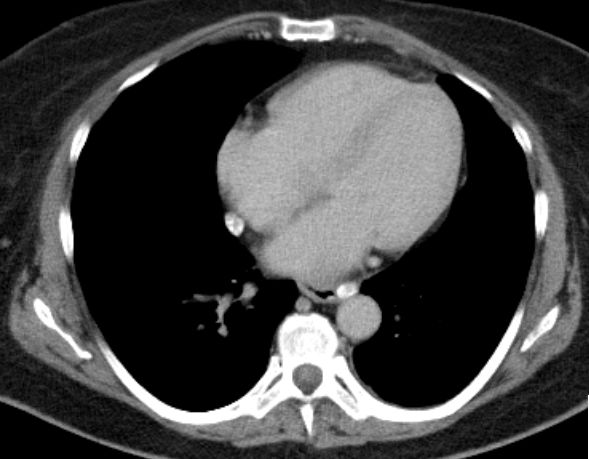

6 Monate später Lebermetastasen.![]() |